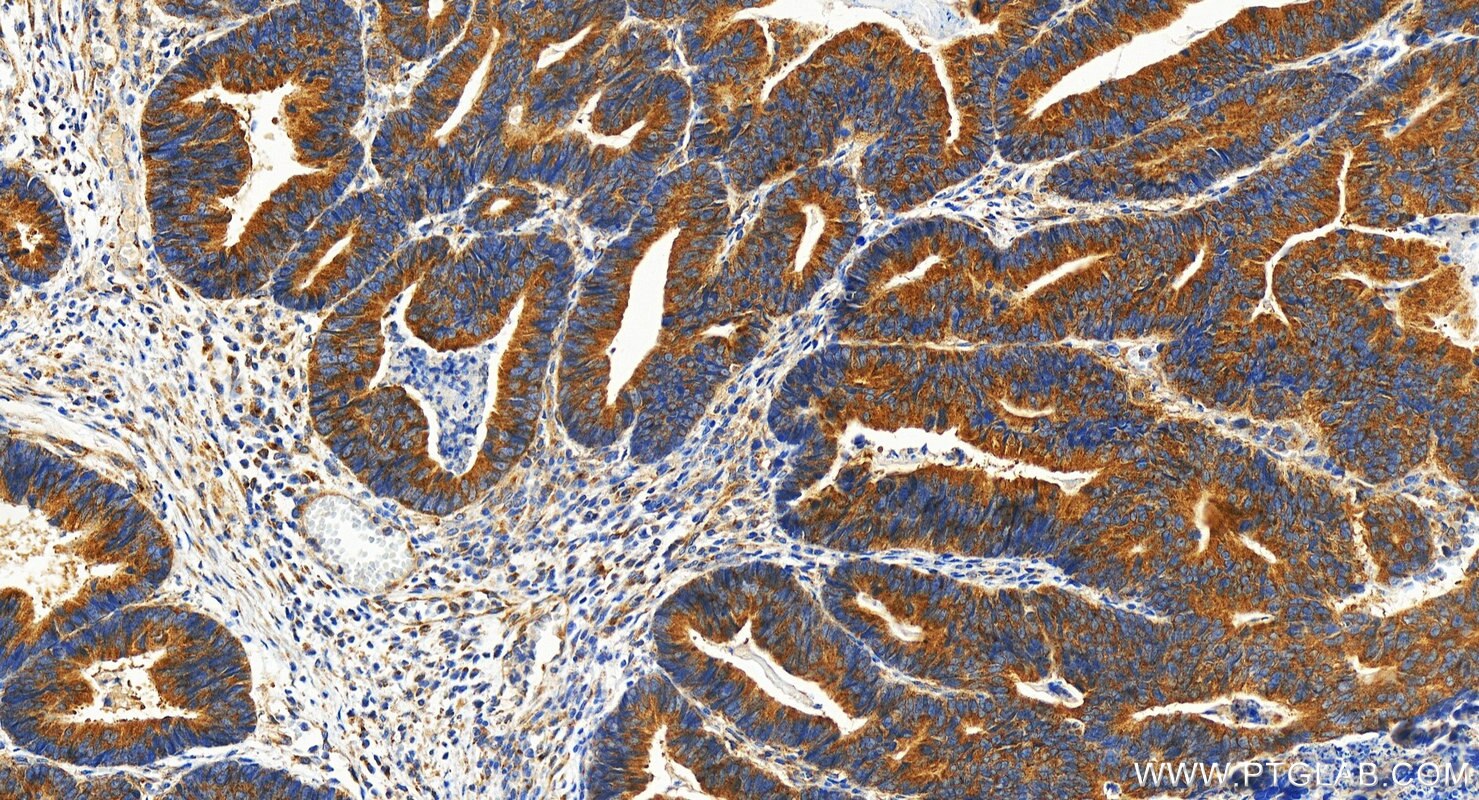

| Positive IHC detected in | human colon cancer tissue, human cervical cancer tissue Note: suggested antigen retrieval with TE buffer pH 9.0; (*) Alternatively, antigen retrieval may be performed with citrate buffer pH 6.0 |

| Immunohistochemistry (IHC) | IHC : 1:1000-1:4000 |